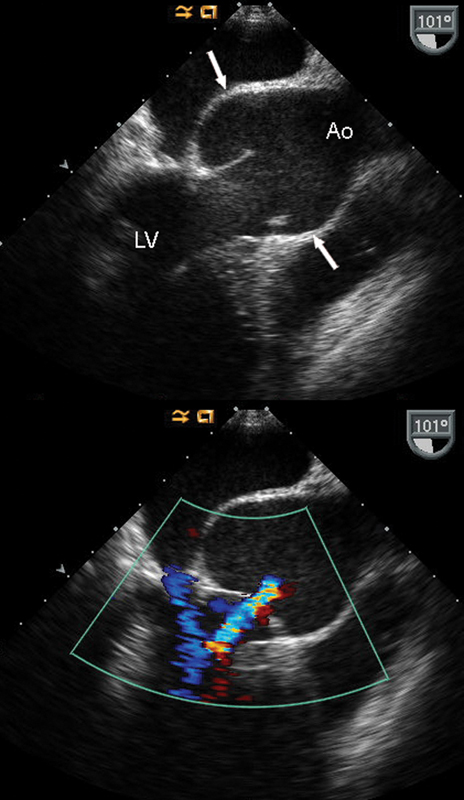

فحوصات تشخيصية لبعض امراض القلب والشرايين التاجية